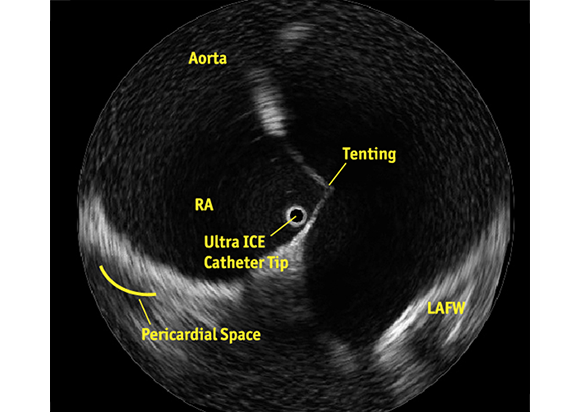

Know Where You Are

ULTRA ICE PLUS catheter positioned in the right atrium, adjacent to the fossa ovalis, visualizing the structures critical to successful transseptal puncture: the septum, aorta, needle position, tenting, and the LAFW.

See What You Want to Avoid

Notice the patient’s reduced Left Atrium, the tenting of the septum and its relationship to the LAFW. The corresponding fluoroscopic image may suggest that puncture has already occurred. However, the ULTRA ICE PLUS image shows that this is not the case and guides the physician to redirect the needle in a puncture angle away from the LAFW.